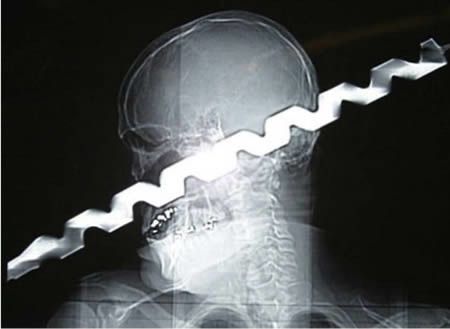

1.

Двое мужчин-строителей упали со строительных лесов. В руках одного из них был пистолет, стреляющий гвоздями, при падении пистолет сработал и выпустил кучку гвоздей в голову второго упавшего. 39-летний Исидро Мехиа ходил с минимальной помощью и говорил немного медленно, потому что речевой центр его мозга был затронут, но его прогресс прекрасен и с реабилитационной терапией он восстановился полностью.